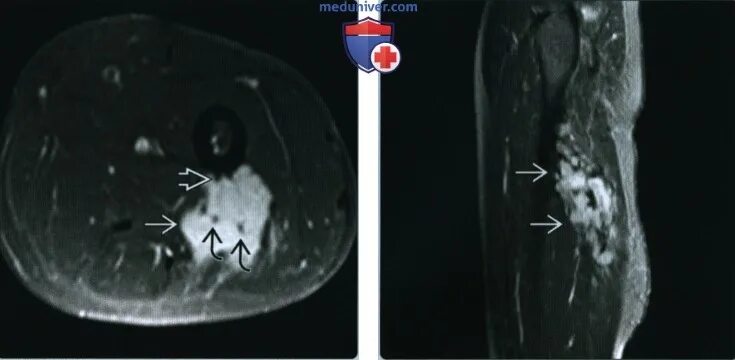

Фиброматоз мягких